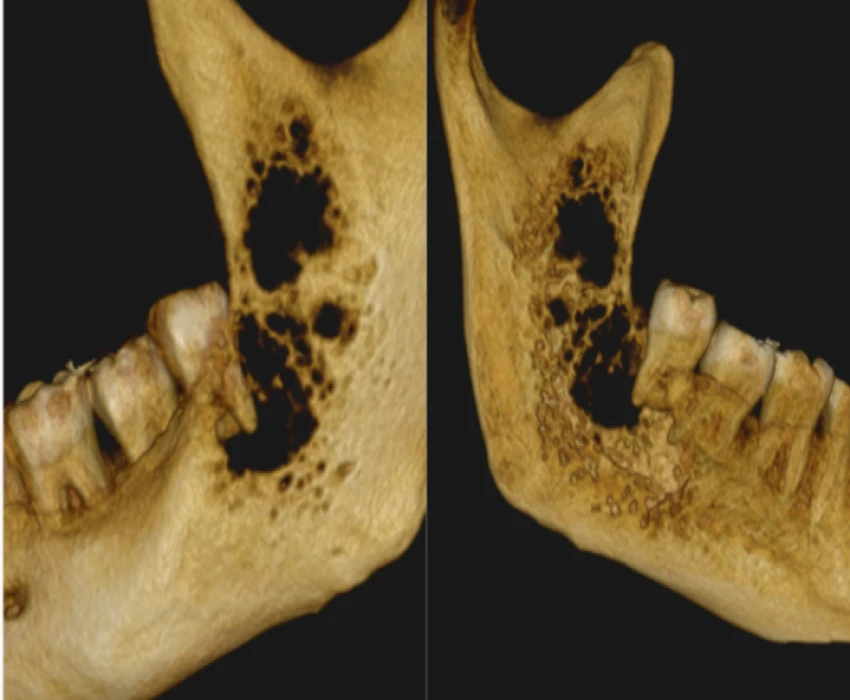

A patient reported to our department with a chief complaint of pain in lower left back region of jaw since 1 month and diagnosed as Carcinoma Involving Left Mandibular Buccal Vestibule and Alveolus Extending Upto Ramus and was treated for the same.

Surgical management was done.